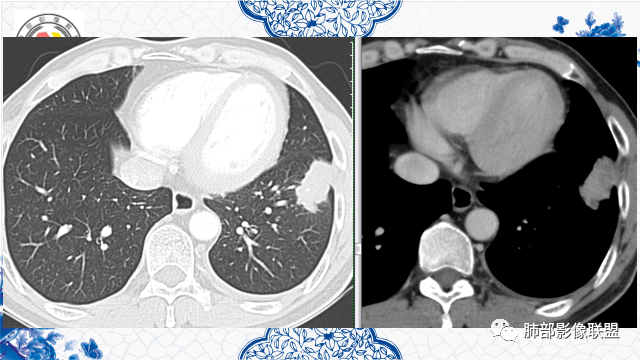

3月前左肺中下野可见结节灶,现CT可见沿支气管走形融合成团片灶,近端支气管进入后截断,病灶整体以平直收缩为主,局部膨隆,与胸膜呈糊墙样改变,病灶周边可见结节,总体分析病灶是结节融合形成,远端大近端小,符合支气管爬行征,强化后其内可见多发低强化区,低强化边界不清,其内未见血管,首先考虑炎性病灶结核,隐球菌分布不符合,但是也可以有,另外恶性不能排除,建议排查结核、隐球菌,如不能明确,穿刺活检是必要的!

良性的依据有五点::第一,周围收缩,凹陷,桃尖,边缘大部分平直,周围卫星灶。第二,栽脏不明确,第三,强化有环形强化的感觉。第四,有支气管爬行的味道。第五,专门提出三个月前胸片多发小结节,三个月后变大成肿块。

增强坏死周围似乎见环形强化的环